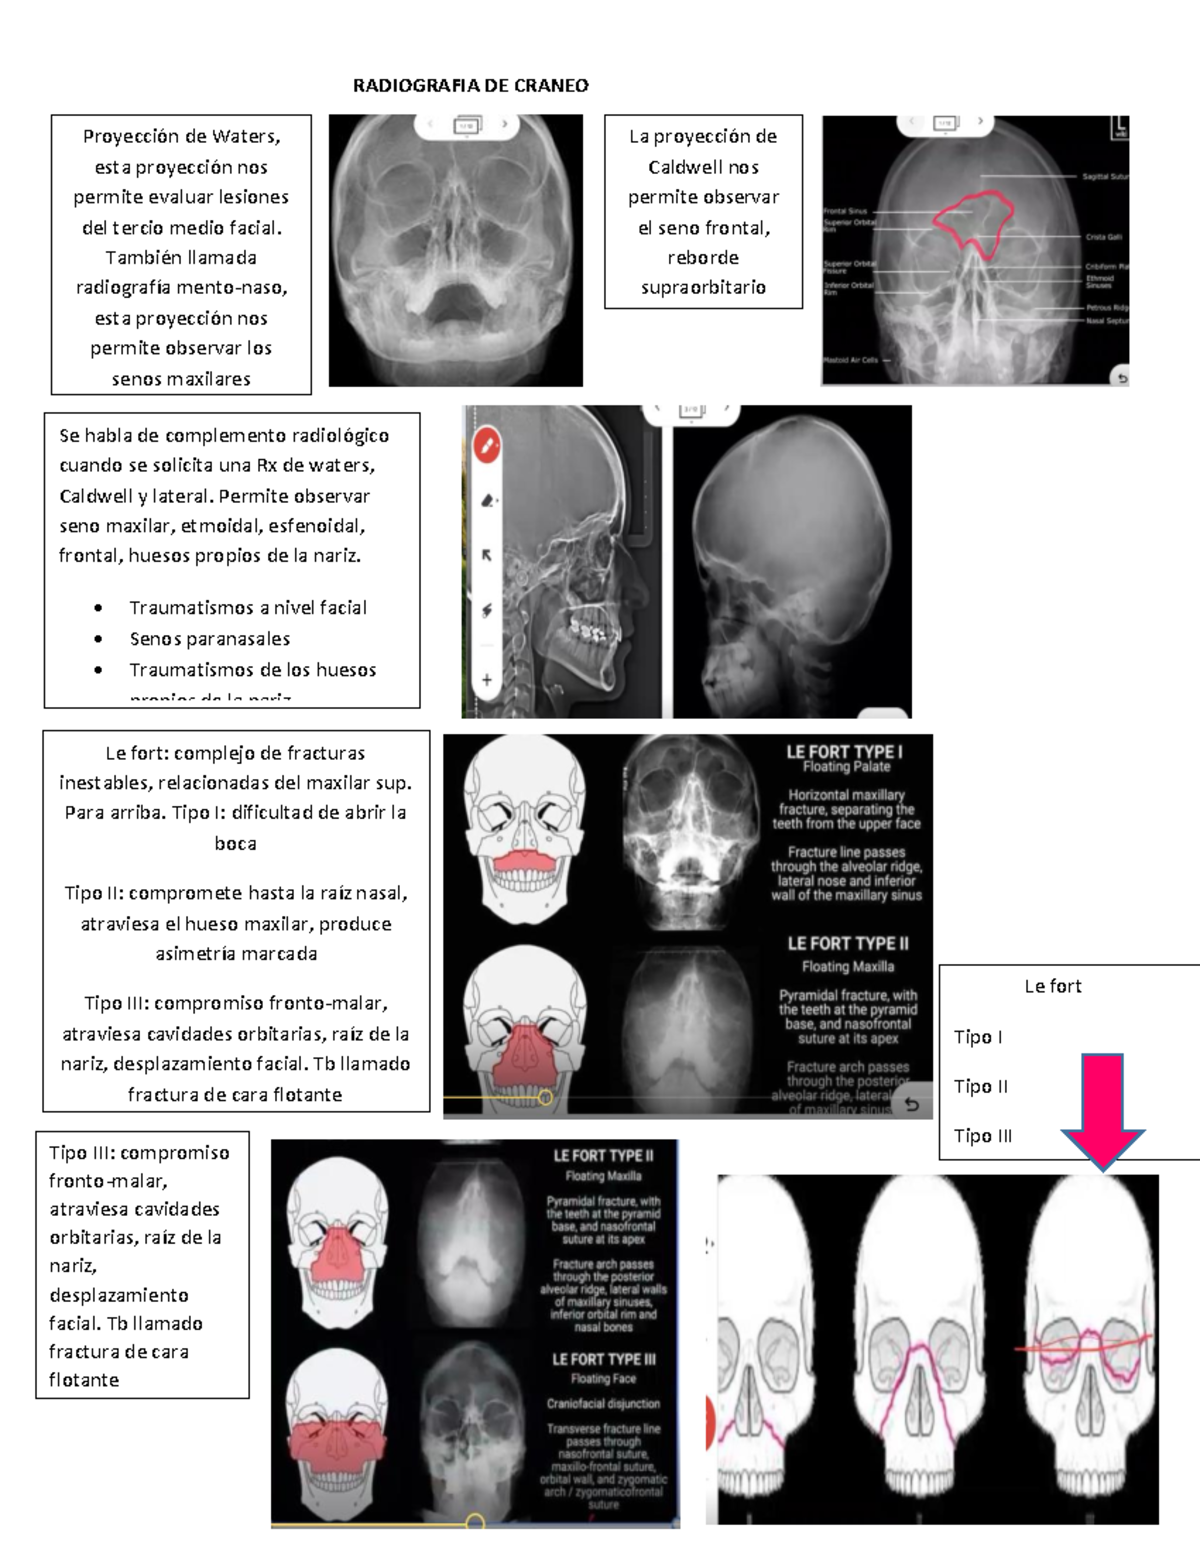

Dx por imagen Craneo Columna RADIOGRAFIA DE CRANEO Proyección de Waters, esta proyección nos

Senos Paranasales Imagenología

Semiologia y radiologia de senos paranasales

Continuum Utilidad de la radiografía en los traumatismos faciales pediátricos

Incidencias de CADWELL y WATERS NeuroMedicine uDocz